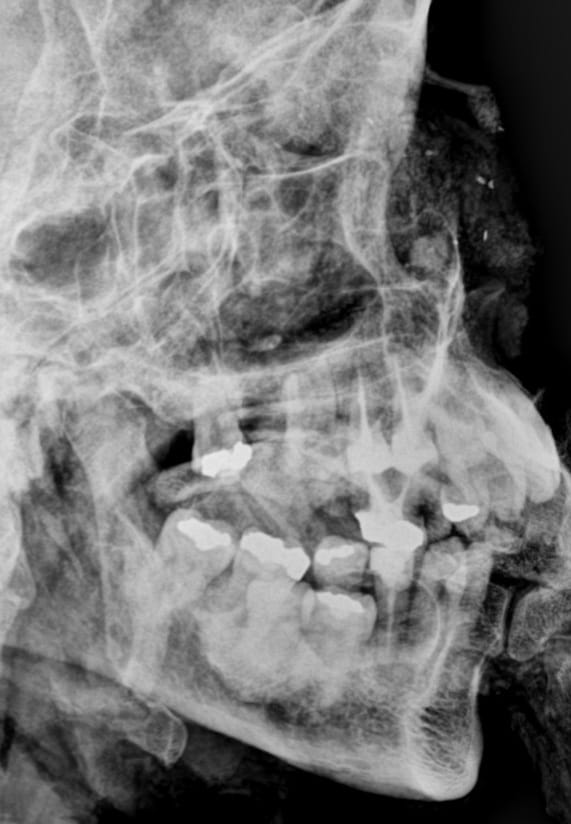

De acordo com os odontolegistas, os dois corpos carbonizados tiveram seus arcos dentários cuidadosamente examinados e radiografados. Desde ontem a equipe do setor de Odontologia Forense vinha trabalhando, realizando várias análises para garantir uma resposta oficial para os familiares das vítimas.

Outro fator que permitiu a realização da identificação foi o fornecimento à Perícia Oficial do prontuário odontológico, fotografias e radiografias produzidos durante atendimentos clínicos odontológicos. Esse material foi cedido pelo cirurgião-dentista Dr. Moisés Omena (CRO-AL 3886), responsável pelo tratamento odontológico da vítima Sra. Maria de Lourdes Bezerra Nunes Marques.

A Identificação de Maria de Lourdes foi possível através da comparação odontolegal entre os trabalhos odontológicos verificados no exame dos arcos dentários do corpo carbonizado e nas radiografias post mortem obtidas deste mesmo corpo no scanner de cadáveres com os dados fornecidos pelo cirurgião-dentista.

Já a segunda vítima, o menor Rafael Nilo dos Santos Nunes, foi identificada através de um trabalho minucioso de estimativa de idade realizado também com o auxílio de radiografias post mortem. Com a conclusão dos exames foi possível emitir as declarações de óbito com a identificação oficial das vítimas.